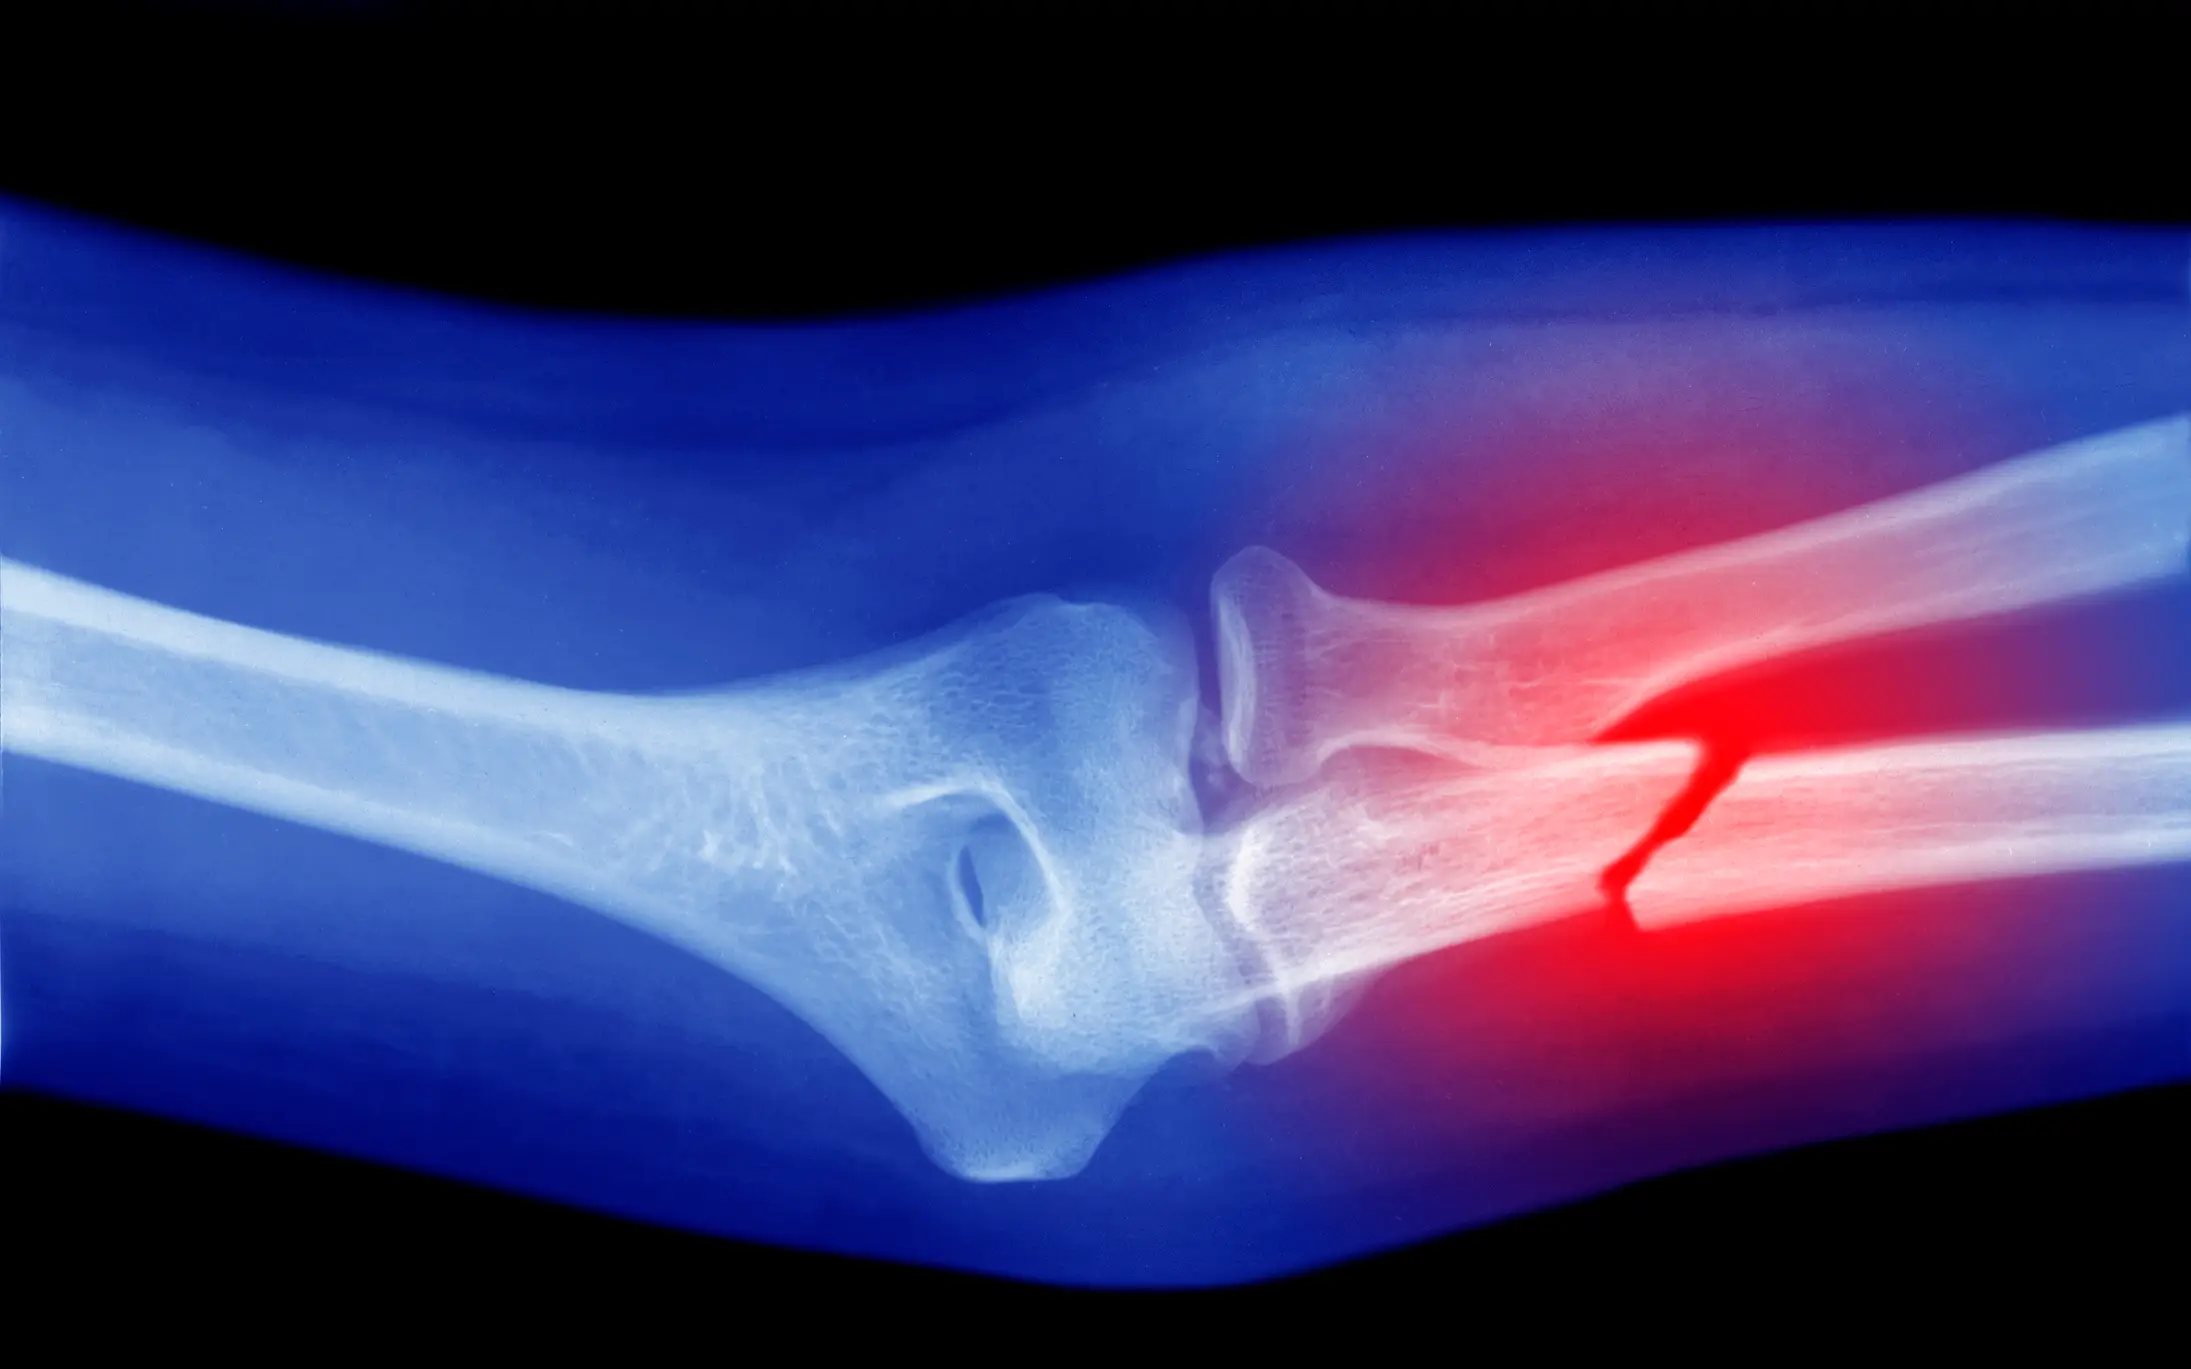

For most people, part of growing up involves falling off the monkey bars in a playground, slipping while walking down the stairs or bashing your ankle while swinging a scooter around, which ends up with a trip to the hospital and a broken bone.

For especially unlucky souls, a freak accident in adulthood has led to several weeks in a plaster cast or on crutches.